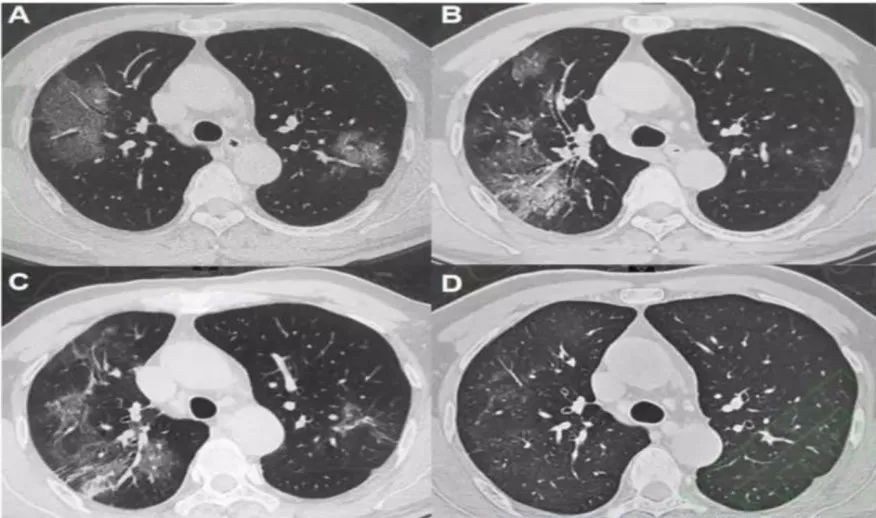

4. 恢复期

2019-nCoV肺炎患者治疗过程中病灶变化较快, CT表现与临床病情紧密相关。部分病例经过1-2周抗病毒抗炎等积极治疗后病变范围缩小,密度减低;同 时在其他肺野也会出现新的斑片状影;病变吸收过程中可出现不规则长索条状影,部分索条影可完全吸收,支气管增粗的程度减轻。部分病例治疗效果不佳,合并其他病原菌感染,肺内病变由局限性进展为多发、弥漫性病变,累及范围明显扩大,密实,合并肺不张、胸腔积液。

图7 57 男岁,SARS-CoV-2核酸检测阳性,A、B、C 、D分别为病程的第 3、8、11、17天。图 D 双肺上叶病灶大部分吸收